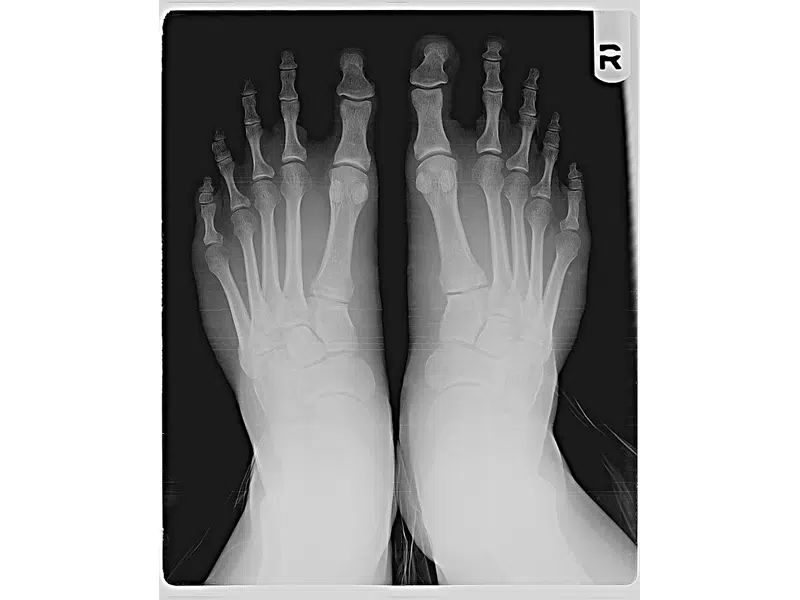

Increasing Capacity for Lab and X-ray Techs